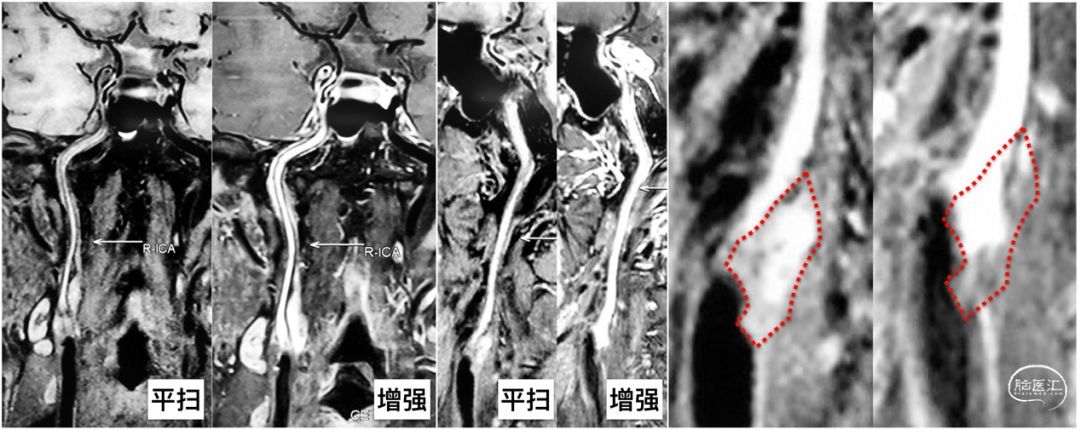

我们又做了高分辨率核磁检查,给我们两个基本信息:

斑块位于ICA起始部,平扫高信号,但增强扫描显示斑块上段强化,下段信号降低;

ICA闭塞以远平扫高信号,并有明显的增强,这是什么斑块?到底闭塞了没有?

我们本就备着复合手术,所以先复查造影看看,还是闭塞。但我选择相信我们无敌的超声团队,果断小切口,打开后触及斑块远端比较软。远端先切开外中膜,保留内膜完整,透过半透明的内膜可见远端管腔内的血流,鲜红色而非血栓的黑色,看来我们的选择是对的![]() 。

手术虽然顺利,但还是存在一些疑问:HRMRI的信号该如何解释?还望有经验的医生不吝赐教![]()

第三个病例,回顾3年前发病的时候,虽然右侧颈动脉当时还是中度狭窄,较左侧为轻,但疑似皮层梗塞提示我们有栓塞的可能性。那时的颈动脉可能就是一个容易复发的易损斑块,正如后来高分辨率核磁所显示的那样,大脂质核心伴斑块内出血。对于颈动脉狭窄而言,除了狭窄度,斑块的稳定性也是我们必须重视的。

,在此也希望华扬主任的团队能够为全国的外科医生培养出更多“火眼金睛”。高分辨核磁对于术前的判断极为重要,几乎可以印证所有的斑块、血栓结构,能够很好地鉴别血栓的不同时期,对于慢血流也有独到的鉴别能力,平扫高信号+均匀强化的特征性信号。建议每位尝试做ICA慢性闭塞再通的医生,无论手术、介入还是复合手术,最好将HRMRI作为必选项。